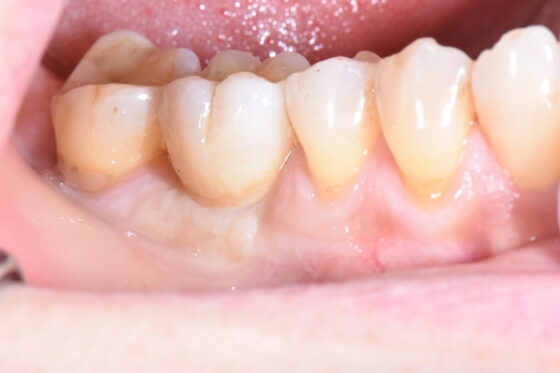

宇部市 歯医者 歯根嚢胞で失った奥歯にインプラント治療